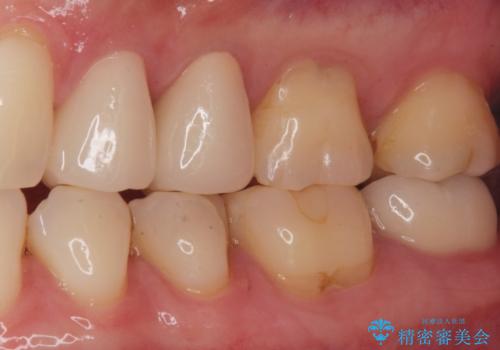

白い被せ物を入れたことにより銀が目立たなくなり

染みることもなくなりました。

ご希望に沿った治療となり大変満足して頂けました。